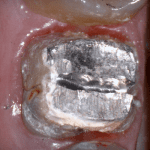

In this clinical video we demonstrate how to scan a molar preparation for the replacement of a crown with recurrent decay and open margins. The molar was root canal treated and the tissue was inflamed. the preparation was imaged and a temporary was fabricated to allow the tissue to heal properly.

The main point of this video is to show how to capture the contacts of the adjacent teeth and the deep marings